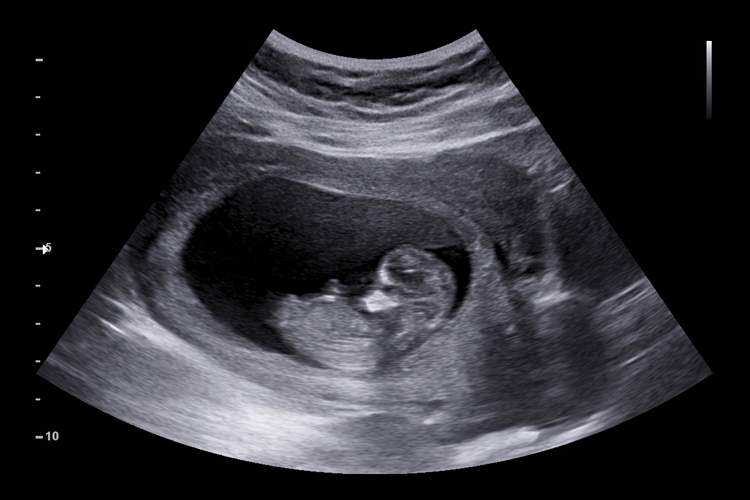

Anche il feto prova dolore e per valutare questo dolore è stata messa a punto una scala specifica chiamata “Fetal-7” che è applicabile nel terzo trimestre di gravidanza

Anche il feto prova dolore e per valutare questo dolore è stata messa a punto una scala specifica chiamata “Fetal-7” che è applicabile nel terzo trimestre di gravidanza e attraverso l’utilizzo di immagini ecografiche e la presenza di specifici segnali sul volto del feto identifica la sofferenza. La procedura di messa a punto della scala e le prove di efficacia della stessa sono stati pubblicati sul The Journal of Pain.

Con lo sviluppo della tecnologia ecografica, è stato possibile ritrovare nei feti le stesse espressioni facciali osservate nei neonati che soffrono di dolore acuto. Con il rapido sviluppo della chirurgia anche nel grembo materno, la questione del dolore nel feto è passata dal timone neuroscientifico e teorico a un’entità pragmatica e clinica.

Recentemente, è stato infatti dimostrato che le espressioni fetali di dolore acuto innescate dall’iniezione intramuscolare di anestetici prima dell’esecuzione di un intervento chirurgico fetale (occlusione fetale tracheale e dilatazione della valvola aortica fetale) potrebbero essere registrate mediante ultrasuoni 4D ad alta definizione diretti al feto.

Sorprendentemente, tutte le espressioni facciali di dolore acuto validate per i neonati potrebbero essere chiaramente identificate nei feti del terzo trimestre. Un altro studio ha infatti dimostrato che con l’esclusione di elementi ridondanti e l’aggiunta di due aggiuntivi, si potrebbe produrre un sistema di punteggio del dolore fetale nei feti del terzo trimestre (la scala Fetal-7), comprendente sette elementi derivati da espressioni facciali. e movimenti ed espressioni della testa: i. “abbassamento delle sopracciglia”; ii. “occhi strizzati”; iii. “approfondimento del solco nasolabiale”; iv. “labbra aperte”; v. “allungamento orizzontale della bocca”; vi. “allungamento verticale della bocca”; vii. “deflessione del collo.